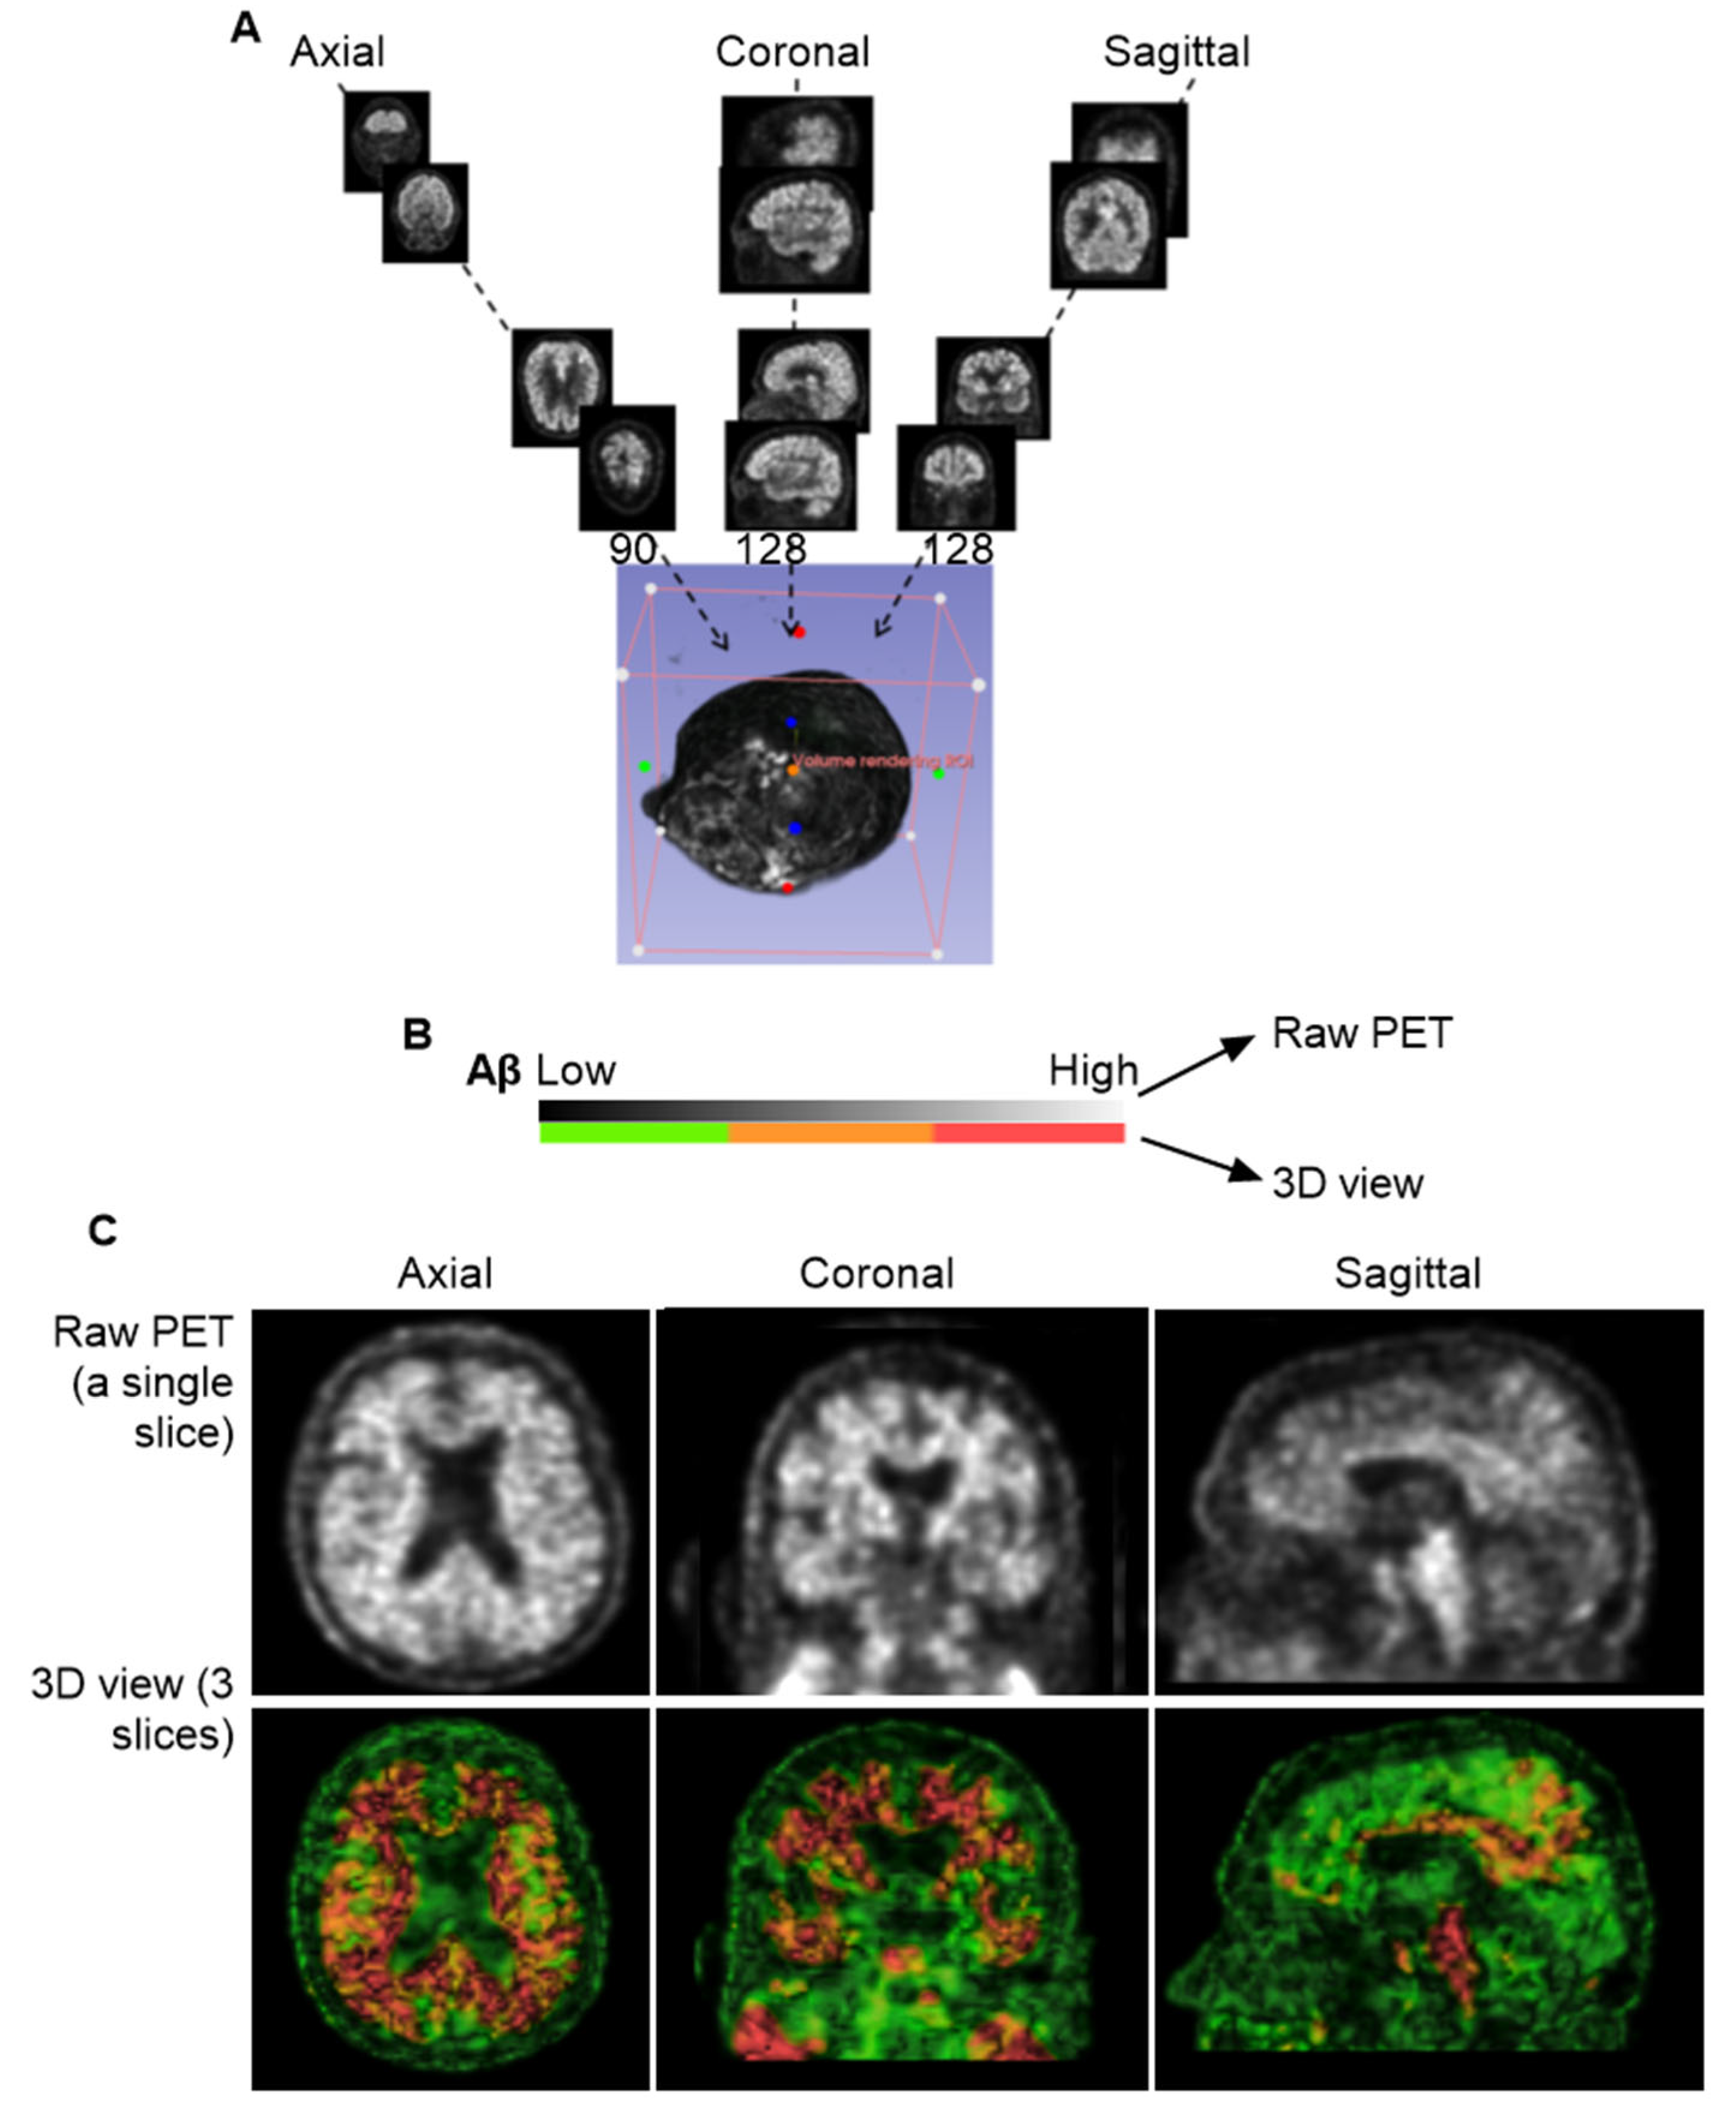

Figure 2A presents static pictures of 3D florbetapir PET scans from six cognitively unimpaired individuals (a) and six individuals with AD (b). MP4 videos for each subject provide dynamic visualization, included in the Supplementary Materials Videos S1 and S2. Aβ signal intensity was visualized using a color-coded scale: green for low expression, yellow to brown for moderate expression, and red for high expression. Since the color-coded scale is relevant to Aβ concentrations, it is likely that analysis of signaling colors could unearth Aβ kinetics in the normal tissues from the high to low concentrations. In the lymphoid tissues, however, the concentrations could be reversely from low to high concentrations due to autonomic regulation. Figure 2B depicts intensity mapping between Aβ signals and anatomies, revealed characteristic Aβ signaling patterns that can be grouped into four distinct ROIs: 1, cranial group; 2, extracranial group in the skull; 3, deep cervical group; 4, superficial cervical group (Figure 2B). Based on color-coded scales, the lowest Aβ signaling was in the skull, while the highest concentrations were observed along the brain ventricular walls, the occipital bones at the skull base, and the cervical lymph nodes (cLNs). Importantly, both CU and AD individuals exhibited consistent spatial distribution patterns, suggesting that the observed organization may reflect a shared anatomical pathway for Aβ clearance.

3.4. Group 3: Deep Cervical Areas

Unlike the skull, Aβ signal intensity in the deep cervical region is heterogeneous (Figure 2A), showing low in some ROIs and high in others. While low-intensity signals in this area also form canal-like networks, they appear more densely clustered than those observed in skull regions. High-intensity Aβ signals were localized to specific anatomical sites, as marked in Figure 6A(I,II). We hypothesized that these elevated signals in the deep cervical region may correspond to anatomical intersections involved in Aβ clearance pathways from the brain to peripheral lymphatic structures. To investigate this, we co-registered PET images with MRI scans from the same individuals to provide anatomical context for the high-intensity signals. This co-registration revealed that prominent Aβ signals were localized to the clivus of the occipital bone at the skull base (Figure 6A(III)). Additionally, high-intensity signals were observed along the internal carotid plexus (Figure 6B), suggesting that Aβ signals may extend beyond the cranial vault into structurally connected extracranial regions.

Figure 6. Group 3: the Deep Cervical Region. (A), High intensity of Aβ signals associated with the clivus bones. Prominent ROI, marked by yellow arrows, was consistently detected across PET scans of most individuals. Images displayed here are representatives of AD-1 (002_S_5018). Single arrow points to a region of high Aβ signal intensity located in the deep cervical area. (I), PET scan of a single slice at axial, coronal and sagittal planes. (II), 3D volume after reconstructing 3 individual slices for thickness. Dashed lines indicate the deep cervical areas. Aβ signal intensities range from green (low) to red (high). (III), Co-registration of PET/MRI reveals that this signal is anatomically aligned with the clivus, a bony structure at the base of the skull, anterior to the brainstem. The clivus is visualized at the intersection of the vertical and horizontal yellow lines across all three imaging planes. (B), PET signals are shown in red, representing Aβ tracer uptake. Images displayed here are representatives of CU-1 (002_S_0259) and AD-1 (002_S_5018). Brown arrays indicate the internal carotid plexus where Aβ signals in the place coregistered with MRIs of CU-1 and AD-1, respectively. The signals were associated with the internal carotid vessels entering the brain cavity. The anatomical illustration was excerpted from the Atlas of the Human Brain [15], and is used here to provide anatomical context for the described structure.